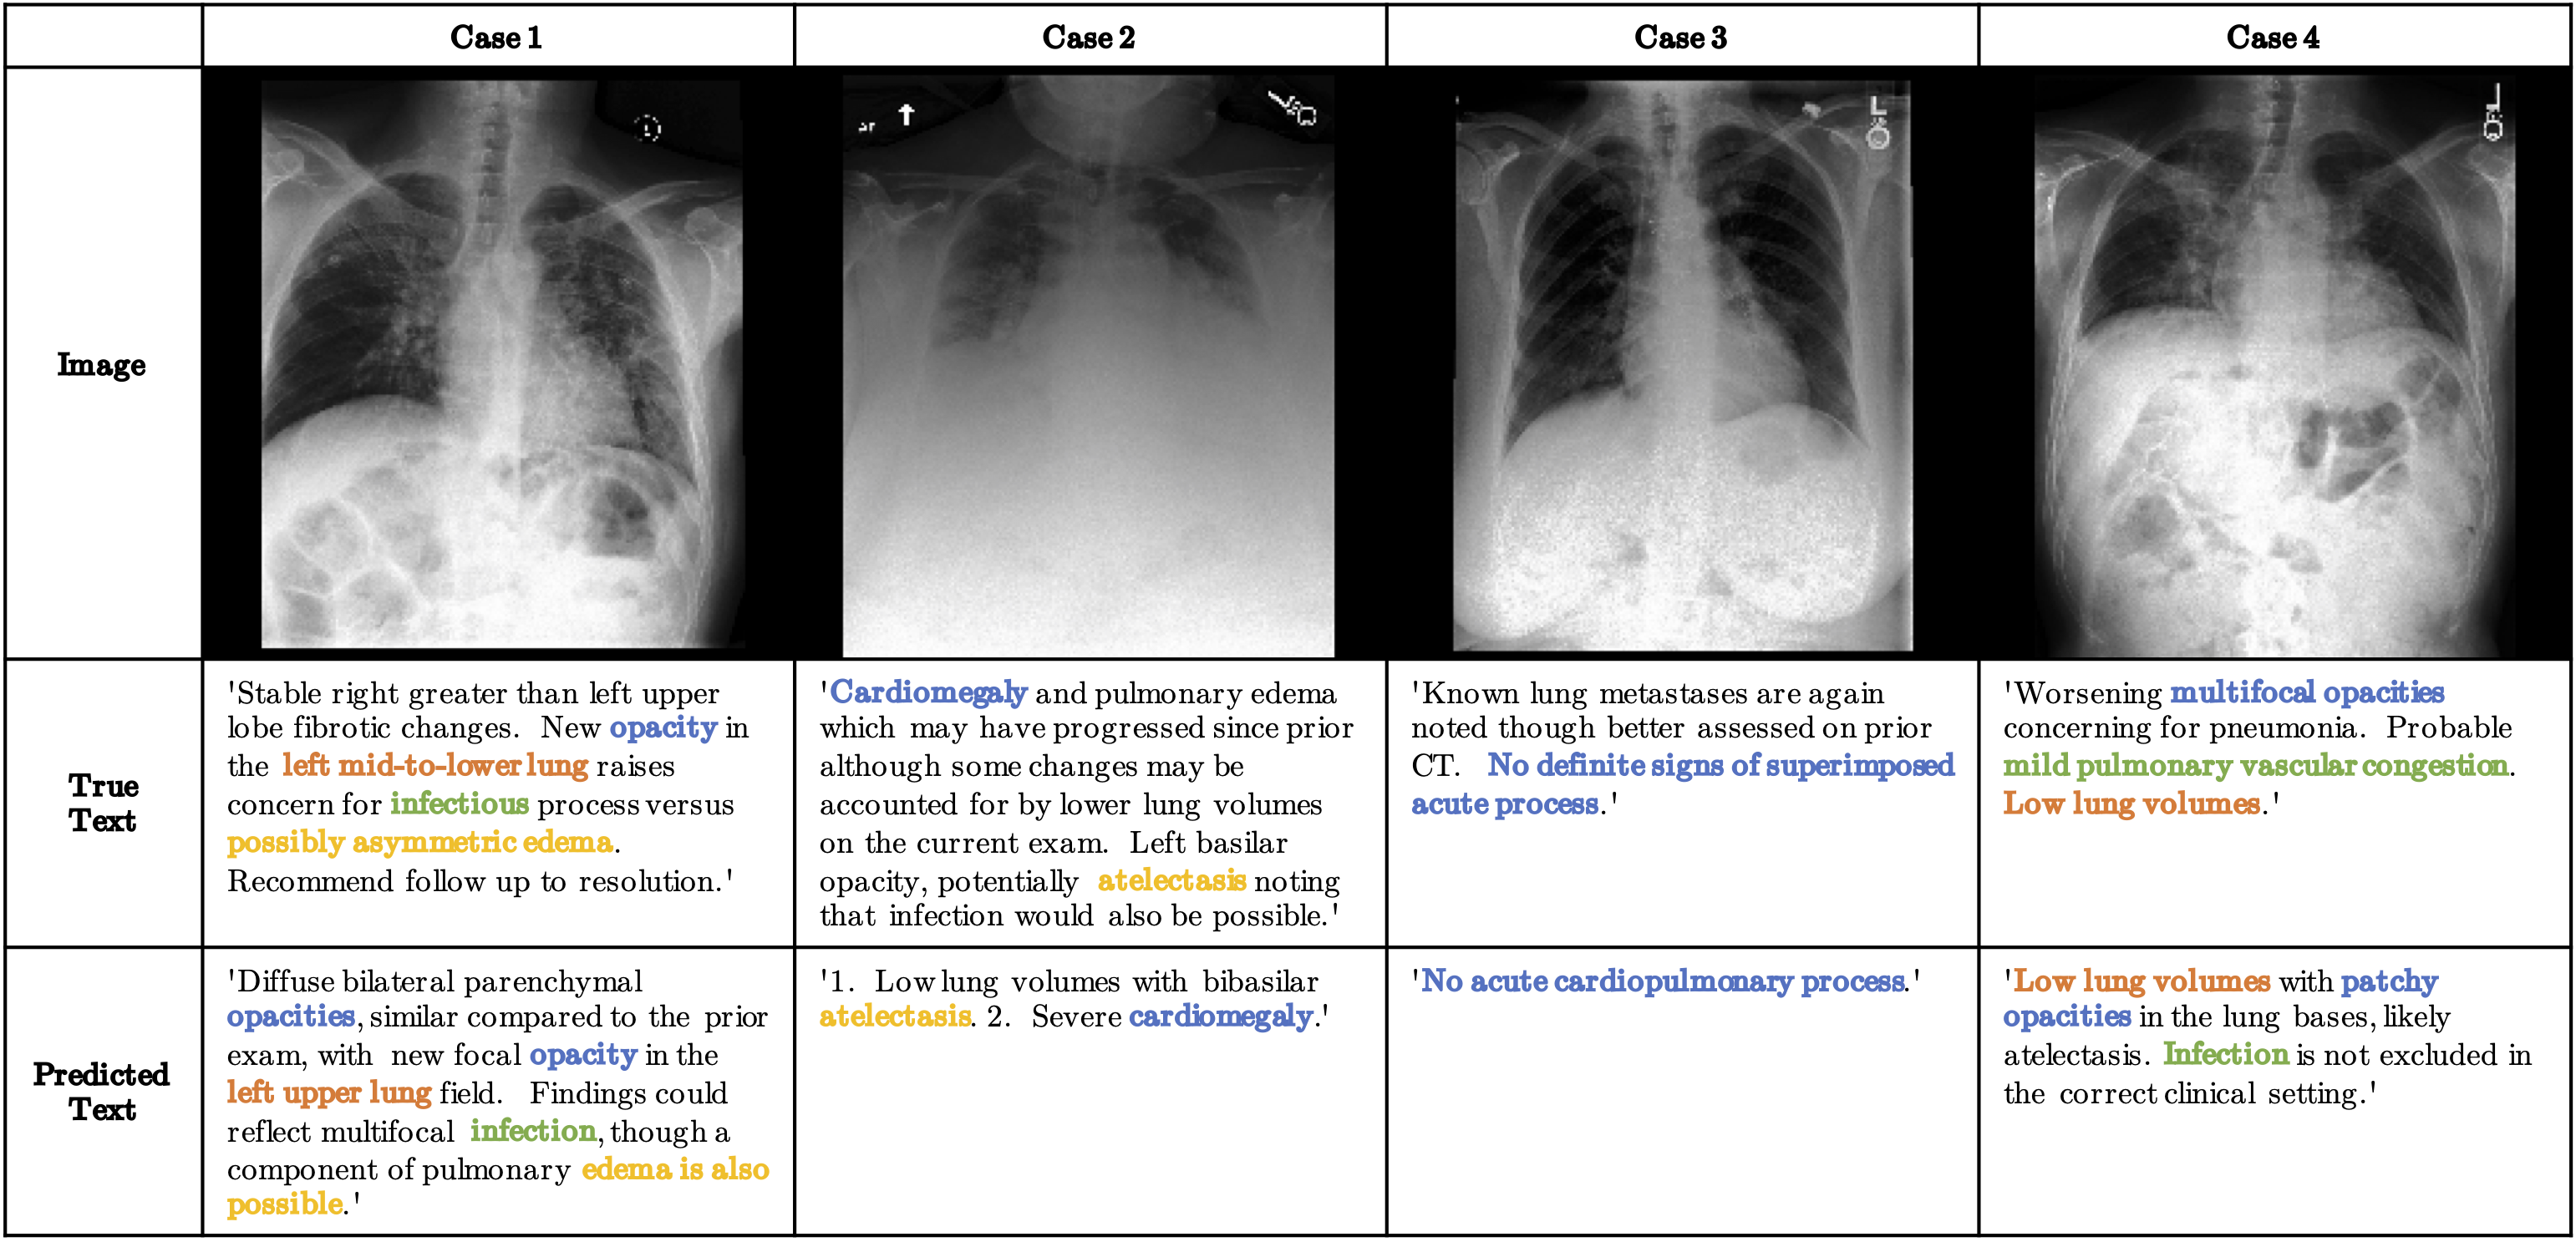

assets/examples.png

ADDED